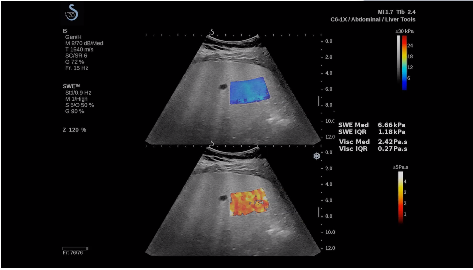

法國聲科影像(SuperSonic Imagine,SSI. Euroniex:FR0010526814)近日發(fā)表公告,宣布其研發(fā)的新一代“極速”超聲成像平臺(UltraFast Imaging),首次實現(xiàn)了肝臟的多項超聲定量評估新指標同步檢測,包括:Att PLUS,SSp PLUS和Vi PLUS等,基本涵蓋肝臟相關病理變化指征的如纖維化、脂肪變、炎癥等。據(jù)悉,此多項新技術新將搭載于新Aixplorer系列E超系統(tǒng)。

E超相關技術已被多項多中心大樣本研究證實對于肝纖維化無創(chuàng)評估有重要意義,同時也可全面應用于乳腺、甲狀腺、肝臟、前列腺、肌骨、婦科等全身各組織器官的定量評估和鑒別診斷。在慢性肝臟方面,聲科E超的肝臟相關定量診斷技術集,于2018年獲得美國FDA認證,成為FDA歷史上首次獲批的單病種超聲全面定量解決方案。